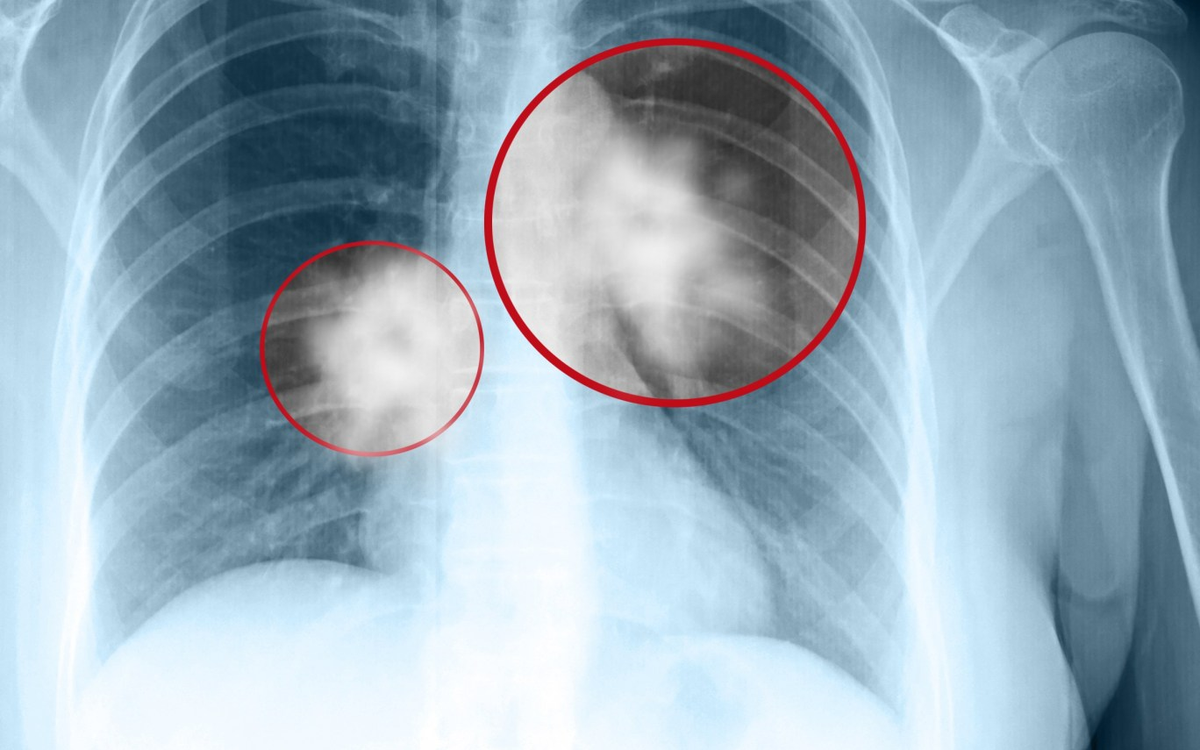

Bài viết trên website Bệnh viện Đa khoa Tâm Anh có sự tư vấn chuyên môn của GS.TS.BS. Ngô Quý Châu cho biết, ung thư phổi (tiếng Anh là Lung Cancer) là loại ung thư khởi phát từ phổi hay còn được gọi là khối u ác tính ở đường hô hấp. Bệnh xảy ra khi một khối u ác tính hình thành trong phổi, phát triển nhanh về kích cỡ dẫn tới xâm lấn, chèn ép các cơ quan xung quanh. Hai lá phổi trong lồng ngực có chức năng hấp thụ oxy khi hít vào và thải carbon dioxide (CO2) khi thở ra.

Ngoài ra, vẫn có trường hợp có thể xuất hiện các khối u phổi lành tính. U lành có về cơ bản có sự khác biệt rất lớn với u ác tính (tế bào ung thư). Tuy nhiên, để xác định chính xác tính chất của khối u, vẫn cần các phương pháp chẩn đoán khoa học và chính xác từ các bác sĩ, chuyên gia y tế.